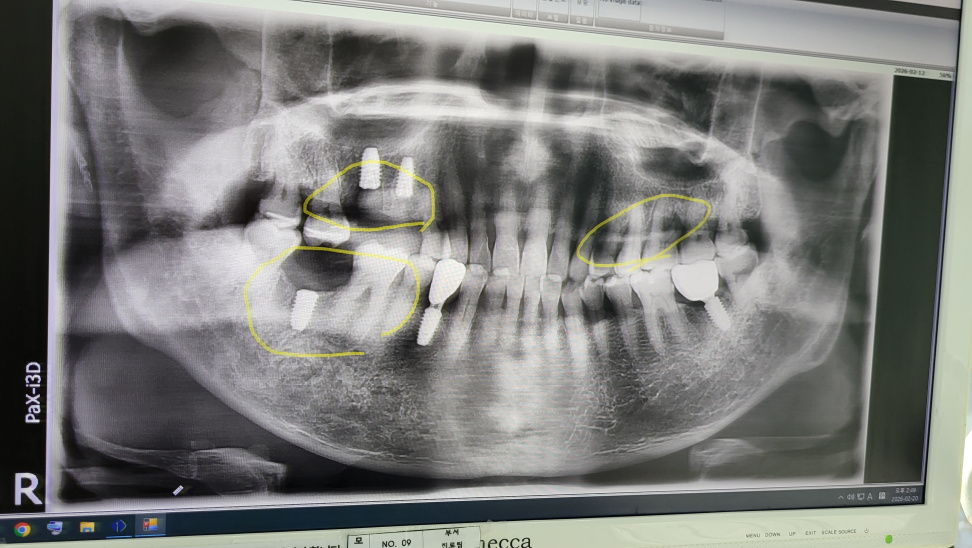

• 2026-02-20 46

• 두번째 임플란트